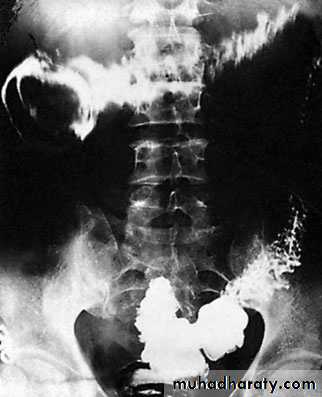

A barium follow-through is contraindicatedin the presence of acute obstruction and may belife-threatening.Impacted foreign bodies may be seen on abdominal radiographs.In gallstone ileus, gas may be seen in the biliary tree, withthe stone visible

Imaging in intussusceptionA soft tissue opacity is often visible in children. A bariumenema may be used to diagnose the presence of an ileocolic intussusception(the claw sign) . An abdominal ultrasound scan has ahigh diagnostic sensitivity in children, demonstrating the typicaldoughnut appearance of concentric rings in transverse section. Acomputerised tomography (CT) scan is also useful in equivocalcases.

Treatment of intussusceptionIn the infant with ileocolic intussusception, after resuscitationwith intravenous fluids, broad-spectrum antibiotics and nasogastricdrainage, non-operative reduction can be attempted usingan air or barium enema . Successful reduction can only be accepted if there is free reflux of air or barium into the small bowel, together with resolution of symptoms and signs in the patient. Non-operative reduction is contraindicatedif there are signs of peritonitis or perforation, there is aknown pathological lead point or in the presence of profoundshock. Surgery is required when radiological reduction has failed or is contraindicated.